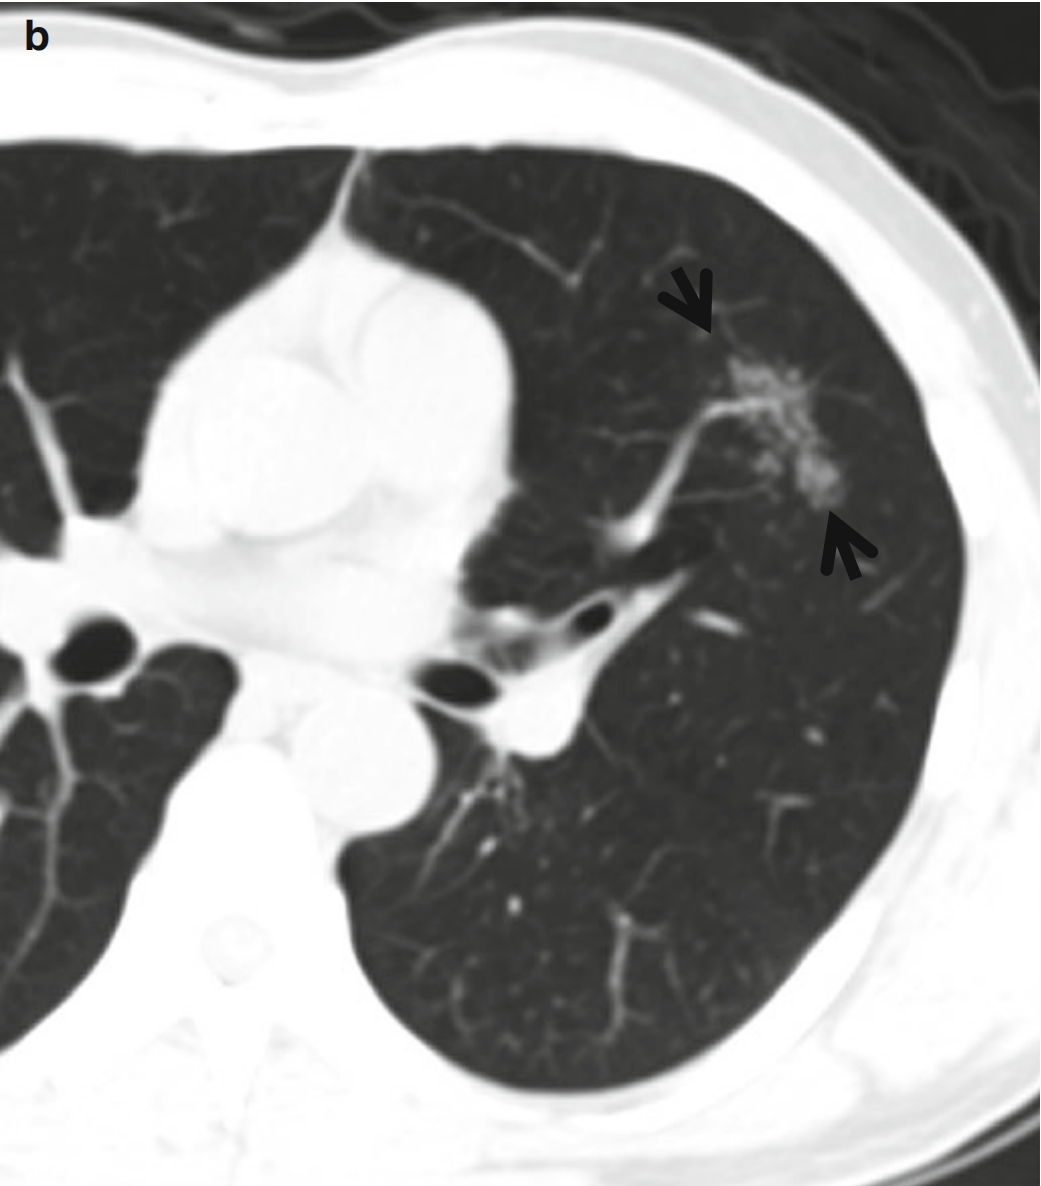

图3 CT星系征。男,53岁,活动性肺结核患者。薄层CT扫描(层厚=2.5mm)分别于主动脉弓水平(a)和奇静脉弓(b)水平肺窗示双肺上叶和左肺下叶背段的星系征(箭头所示)。